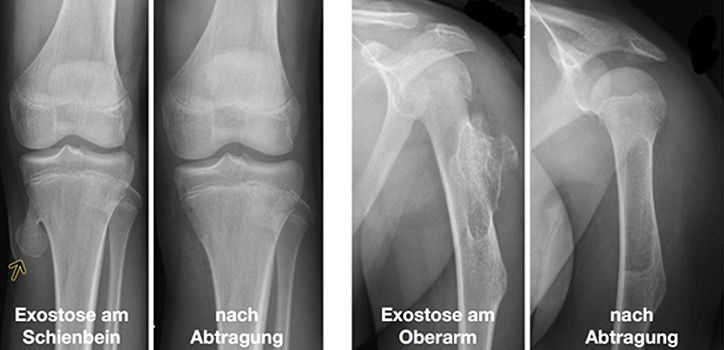

Unter Exostose versteht man eine abgegrenzte Zubildung von kompakter Knochensubstanz mit Wachstum nach außen. Sie können an den verschiedensten Knochen auftreten und ein breitbasiges oder spornhaftes Wachstum aufweisen. Bei der sogenannten Exostosenkrankheit treten viele verschiedene Knochentumoren auf, bei denen eine bösartige Entdifferenzierung nicht vollkommen ausgeschlossen ist. In der Regel finden sich jedoch einzelne Exostosen, insbesondere am Knie, die mit der chirurgischen Entfernung bei o.g. Beschwerden therapiert sind.